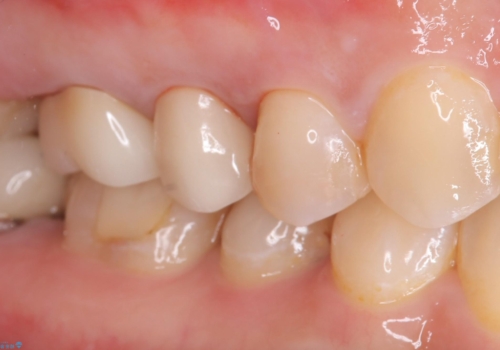

適合不良により汚れが溜りやすく歯肉が腫れている状態だったため、審美性を考慮しセラミックインレーでのやり替えとなりました。

現在入っているインレー・CR裏層を除去し、再度CR裏層・セラミックインレー形成しました。